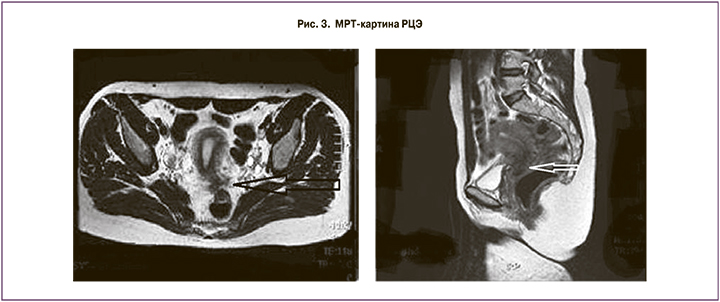

МРТ для данной патологии является практически самым информативным неинвазивным методом исследования. Возможность значительной детализации патологического процесса и выявления нарушений анатомии органов малого таза на фоне распространенного инфильтративного эндометриоза, получаемая при МРТ, позволила поставить правильный диагноз. Исследования проведены на МР-томографе Magnetom Hamone фирмы Siemens (Германия). Критериями оценки распространения заболевания были: локализация, размеры, структура патологического очага, глубина инвазии вовлеченного в патологический процесс органа, прорастание эндометриоидной ткани в просвет влагалища, степень распространения в ректовагинальном пространстве, глубина инвазии в стенку толстой кишки с наличием или отсутствием поражения слизистой оболочки, наличие участков синхронного поражения толстой кишки.

При РЦЭ у пациенток диагностированы эндометриоидные инфильтраты в позадиматочном пространстве с вовлечением шейки матки диаметром до 2,0 см. При поражении кишки диагностирована вовлеченность кишечной стенки в инфильтративный процесс у 13 женщин, из них у 3 пациенток – до слизистого слоя, у 5 пациенток – до подслизистого слоя и у 5 пациенток – до мышечного слоя.

МРТ-картина может быть представлена в разных вариациях, в основном выражена в виде объемного образования с инфильтрацией задней стенки матки, широких связок матки, крестцово-маточных связок, брюшины Дугласова пространства, с фиксацией кишки и заднего свода влагалища (рис. 3).

Образование может распространиться на стенку кишки с признаками прорастания или без них. При эндометриоидных кистах яичников МРТ-картина представлена в виде образования в толще яичника неоднородной структуры с кистозными включениями и геморрагическим содержимым.

С помощью МРТ органов малого таза можно диагностировать не последствия прогрессирующего заболевания, а вовлеченность в инфильтрат серозной/мышечной стенки кишки. Это позволяет вовремя проводить менее травматичную операцию и избежать таких осложнений, как стеноз кишки разных стадий.